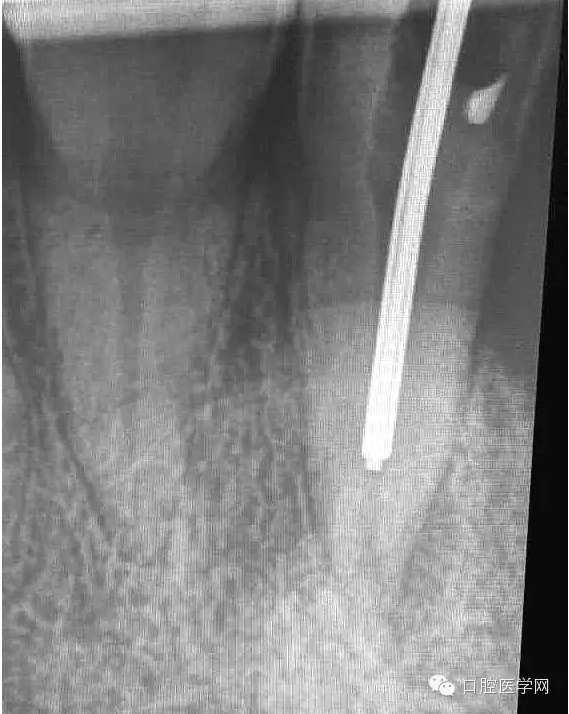

4.準(zhǔn)備放置橡皮障(由于拍片是較遠(yuǎn),所以,橡皮章暫時(shí)取下),去除暫封材料。在顯微鏡放大視野中,蔣調(diào)拌好MTA輸送至根尖部。

5.待MTA凝固后進(jìn)行熱牙膠充填。